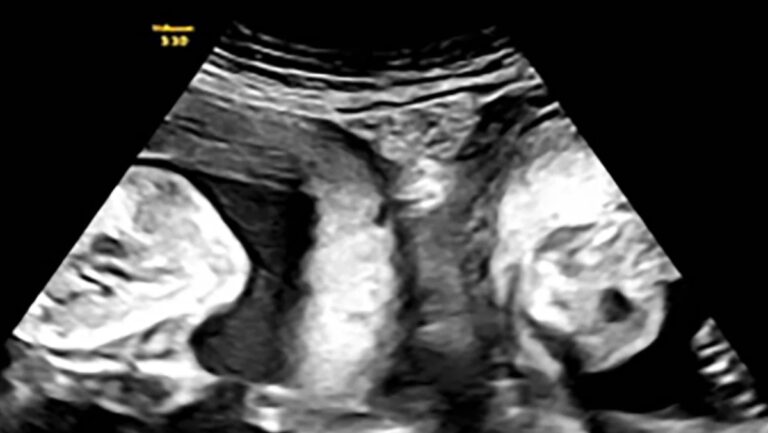

Μια γυναίκα με δύο μήτρες γέννησε δίδυμα, ένα από κάθε μήτρα, τον περασμένο μήνα σε νοσοκομείο της βορειοδυτικής Κίνας, σύμφωνα με αξιωματούχους του τομέα της υγείας και κρατικά μέσα ενημέρωσης. Η Li γέννησε ένα αγόρι και ένα κορίτσι με καισαρική τομή, όπως ανακοίνωσε το Λαϊκό Νοσοκομείο Xi’an στην επαρχία Shaanxi, κάνοντας λόγο για ένα περιστατικό που συμβαίνει «μια φορά στο εκατομμύριο».

Η ιστορία της έγινε viral στα κινεζικά μέσα κοινωνικής δικτύωσης, με περισσότερες από 50 εκατομμύρια προβολές τις τελευταίες ημέρες. Το νοσοκομείο αποκάλυψε επίσης ότι η νεαρή μητέρα είχε μείνει έγκυος άλλη μια φορά αλλά είχε αποβάλλει. Τον Ιανουάριο, όμως, η Li έμεινε ξανά έγκυος και ανακάλυψε κατά τη διάρκεια ενός υπερηχογραφήματος ότι κυοφορούσε δίδυμα – ένα σε κάθε μήτρα.

Μετά από «στενή και αυστηρή» ιατρική παρακολούθηση, η γυναίκα γέννησε με «επιτυχία» ένα αγόρι βάρους 3,7 κιλών και ένα κορίτσι βάρους 3,1 κιλών, σύμφωνα με το νοσοκομείο.